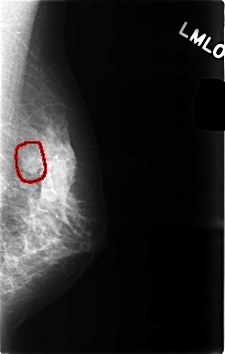

FILE: C_0494_1.LEFT_MLO.OVERLAY

TOTAL_ABNORMALITIES 1

ABNORMALITY 1

LESION_TYPE MASS SHAPE OVAL MARGINS CIRCUMSCRIBED

ASSESSMENT 3

SUBTLETY 5

PATHOLOGY BENIGN

TOTAL_OUTLINES 1

BOUNDARY